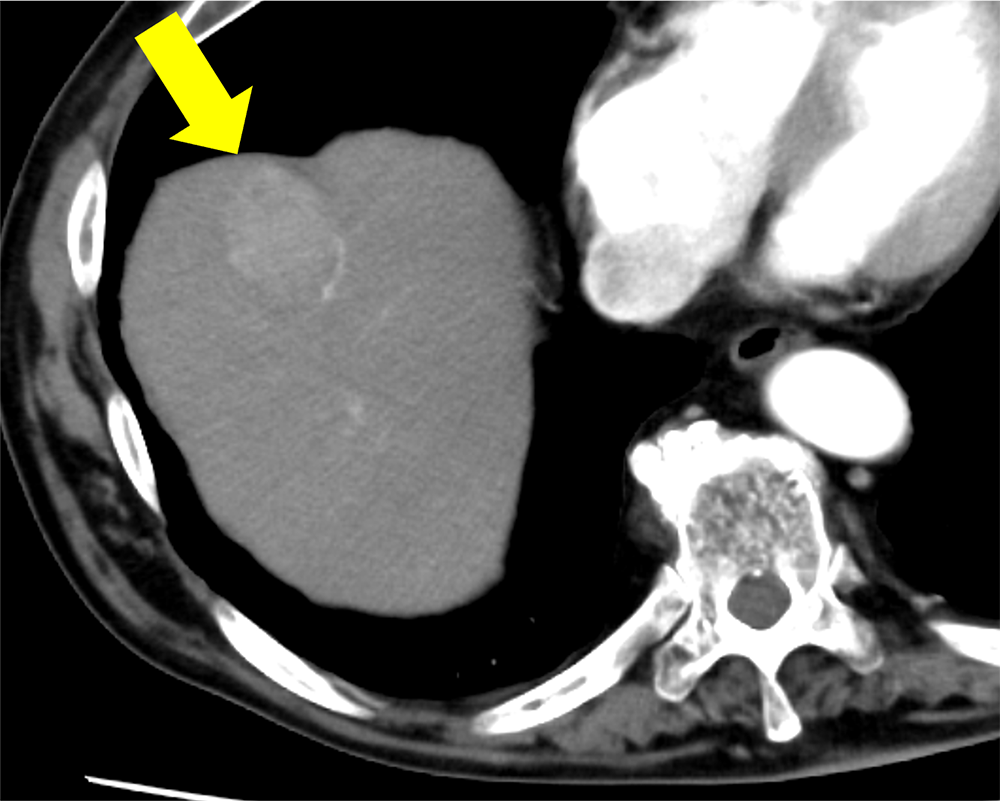

アルコール性肝障害の既往あり。人間ドックの腹部超音波検査で肝腫瘤を指摘され、撮像された造影CTで肝S8の多血化肝細胞癌と診断とされた。単発の病変であり、腹腔鏡下肝S8亜区域切除術が施行された。術後3日目に腹壁瘢痕ヘルニアによる小腸閉塞があり、イレウス解除および腹壁瘢痕ヘルニア修復術が施行された。以降は腫瘍の再発なく経過観察を継続している。

CT技術や撮像プロトコル設定について

今回の造影CTでは造影剤注入を一定速度で注入するのではなく、注入速度を連続的に減少させながら注入する可変注入を用いている。造影剤の総量や注入時間は変化させず、注入速度のみを変化させるため、通常注入と比べて注入開始時の速度は上昇し、終了時の速度は低下する。つまり注入の前半により多くの造影剤を注入し、後半に注入される造影剤は減少する。通常注入を行った場合、動脈相の撮像時点では注入された造影剤の一部は病変には到達しておらず、多血化の評価に活用されている造影剤量は想定よりも少ない可能性があるが、可変注入で注入前半に多くの造影剤を注入することで、より多くの造影剤を多血化の評価に活用することができる。また従来の注入法と比べて可変注入法では大動脈の造影効果のピークが前倒し、ピークのCT値も上昇する。これらにより多血化肝細胞癌の造影効果が上昇し、腫瘍と背景肝のコントラストが上昇する。また従来法では早期動脈相では腫瘍の造影効果は通常得られないが、可変注入法では早期動脈相から腫瘍の造影効果が得られ、まだCT値が上昇していない背景肝とのコントラストが良好となり、多血化肝細胞癌の検出能を向上させる可能性がある。